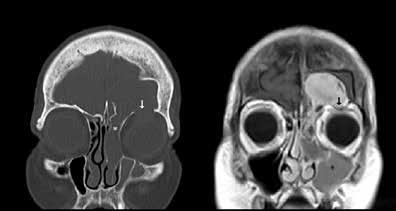

Figure 1. A: Axial CT image in bone windows demonstrates opacification of the frontal sinus with areas of thinning and frank erosion of the posterior cortex. B: Axial T1-weighted gadolinium-enhanced image at approximately the same level shows an avidly enhancing mass protruding intracranially through the bony defect with mild mass effect on the left frontal lobe. The mass abuts invade underlying enhancing dura mater (arrow).

The mass demonstrated intracranial extension, with much of the posterior cortex of the left frontal sinus eroded or thinned. The mass abutted the left frontal dura and created mild mass compression of the underlying brain. There was enhancement of the dura but no evidence of invasion or brain parenchymal involvement (figure 1). The midline component of the mass protruded anteriorly into the adjacent scalp soft tissues, with erosion and thinning of the anterior cortex (figure 2). A small portion of the mass appeared to extend through and widen the frontoethmoidal recess on the left. The inferior portion of the mass also eroded the roof of the left orbit, with extension into the extraconal orbital compartment and compression of the superior rectus muscle (figure 3).

Figure 2. A: Sagittal CT in bone windows demonstrates erosion of both the anterior and posterior cortex of the frontal sinus (arrows). B: Unenhanced T1-weighted sagittal MRI demonstrates the lowsignal mass protruding into the subcutaneous soft tissues, resulting in an obvious cosmetic deformity.

Figure 3. A: Coronal CT in bone windows demonstrates erosion of the left orbital roof (white arrow), with expansion of the left frontoethmoidal recess (white asterisk). B: Corresponding gadolinium-enhanced of mucocele formation.